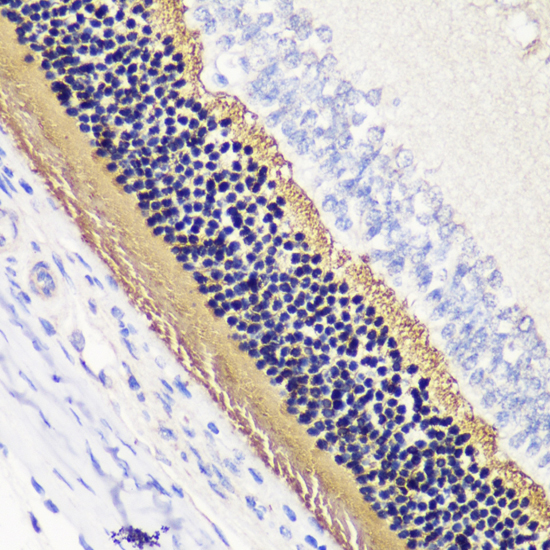

Immunohistochemistry of paraffin-embedded rat retina using PDC antibody.

应用详情:WB 1:500 - 1:2000

IHC 1:50 - 1:200